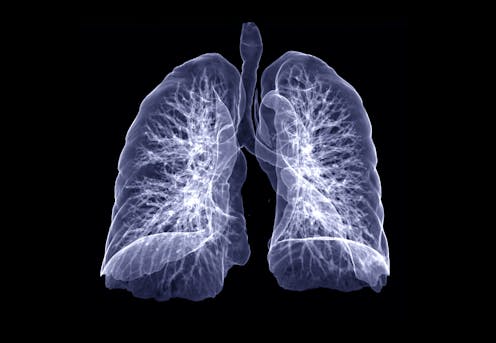

Not all breathing problems are related to the lungs, but in many cases the lungs are affected. Looking at the lungs’ basic functions and how they can be affected by disease may help clarify what is on the horizon for some patients after a COVID-19 infection.

The main function of the lungs is to bring oxygen-rich air into the body and expel carbon dioxide. When air flows into the lungs, it is brought into close proximity with the blood, where oxygen diffuses into the body and carbon dioxide diffuses out.

This process, as simple as it sounds, requires an extraordinary coordination of air flow, or ventilation, and blood flow, or perfusion. There are over 20 divisions in your airway, starting at the main windpipe, or the trachea, all the way out to the little balloons at end of the airway, called alveoli, that are in close contact with your blood vessels.

By the time a molecule of oxygen gets down to the end of the airway, there are about 300 million of these little alveoli it could end up in, with a total surface area of over 1,000 square feet (100 square meters) where gas exchange occurs.

Matching ventilation and perfusion rates is critical for basic lung function, and damage anywhere along the airway can lead to difficulty breathing in a number of ways.